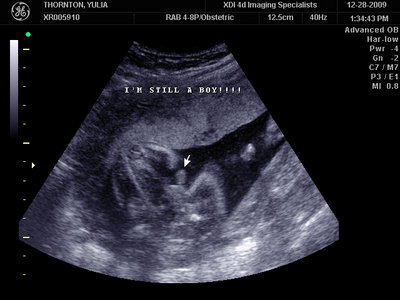

Ну ладно, тогда и я нашего писюна покажу  Надеюсь, Джеффри на меня не обидится Вот это в 23 недели: (там оборудование переключалось из режима 3Д в обычный 2Д)

MY BABY SONO!_2_15.JPG [ 112.35 КБ | Просмотров: 1040 ]

Sweetheart75 писал(а): Ну ладно, тогда и я нашего писюна покажу  Надеюсь, Джеффри на меня не обидится Вот это в 23 недели: (там оборудование переключалось из режима 3Д в обычный 2Д) Oоо, такое достоинство невозможно не заметить  А в 30 недель так вообще!